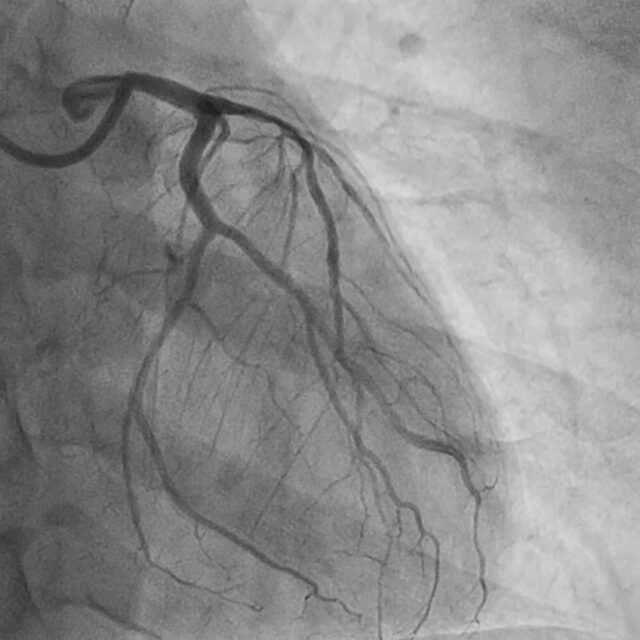

Bild einer Herzkatheteruntersuchung (Coronary Angiography : CAG)